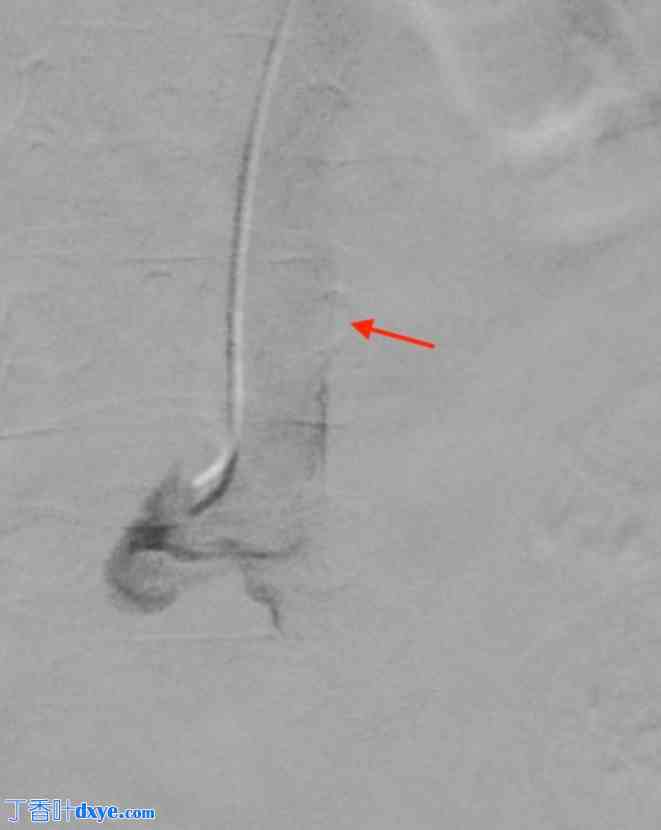

一名43岁男性患者因右肾绞痛和发热入院。非增强CT扫描显示肾盂内有一枚2.5厘米的梗阻性结石(图1)。患者接受了静脉抗生素治疗,介入放射科医生在中肾盏内插入了一根导尿管,引流出脓性分泌物。三周后,一位经验丰富的泌尿内镜医师利用预先建立的导尿管通道,行俯卧位经皮肾镜取石术(PCNL)。术中,首先将一根Roadrunner PC亲水导丝(Cook Medical)经导尿管送入中肾盏,试图将导丝穿过嵌顿结石(图2)。随后取出导尿管。接着,将一根Kumpe 5 Fr通路导管(Cook Medical)沿导丝置入,旨在引导其到达近端输尿管。透视下经Kumpe导管注射造影剂,可见一粗大的管状结构,造影剂迅速向上排出(图3)。在进行增强透视检查后,确认Kumpe导管尖端位于下腔静脉腔内(图4)。随即召开紧急多学科会诊,包括泌尿内镜医师、血管外科医师、介入放射科医师和麻醉医师。患者血流动力学稳定,无活动性出血或呼吸压力升高的迹象。在注射造影剂的同时,小心地将Kumpe导管回撤至肾中盏,未发生经导管进入肾单位或腹膜后间隙的出血。随后,介入放射科医师通过新建立的通道将8 Fr NT导管插入肾上盏。术中患者血流动力学稳定。术后静脉注射造影剂的CT扫描未见造影剂晕染或出血迹象。之后,患者成功接受了经皮肾镜取石术(PCNL),从肾上盏取出结石。

图 3.

经 Kumpe 导管注射造影剂后,可见一个粗大的管状结构。

图 4.

Kumpe 导管位于下腔静脉内。